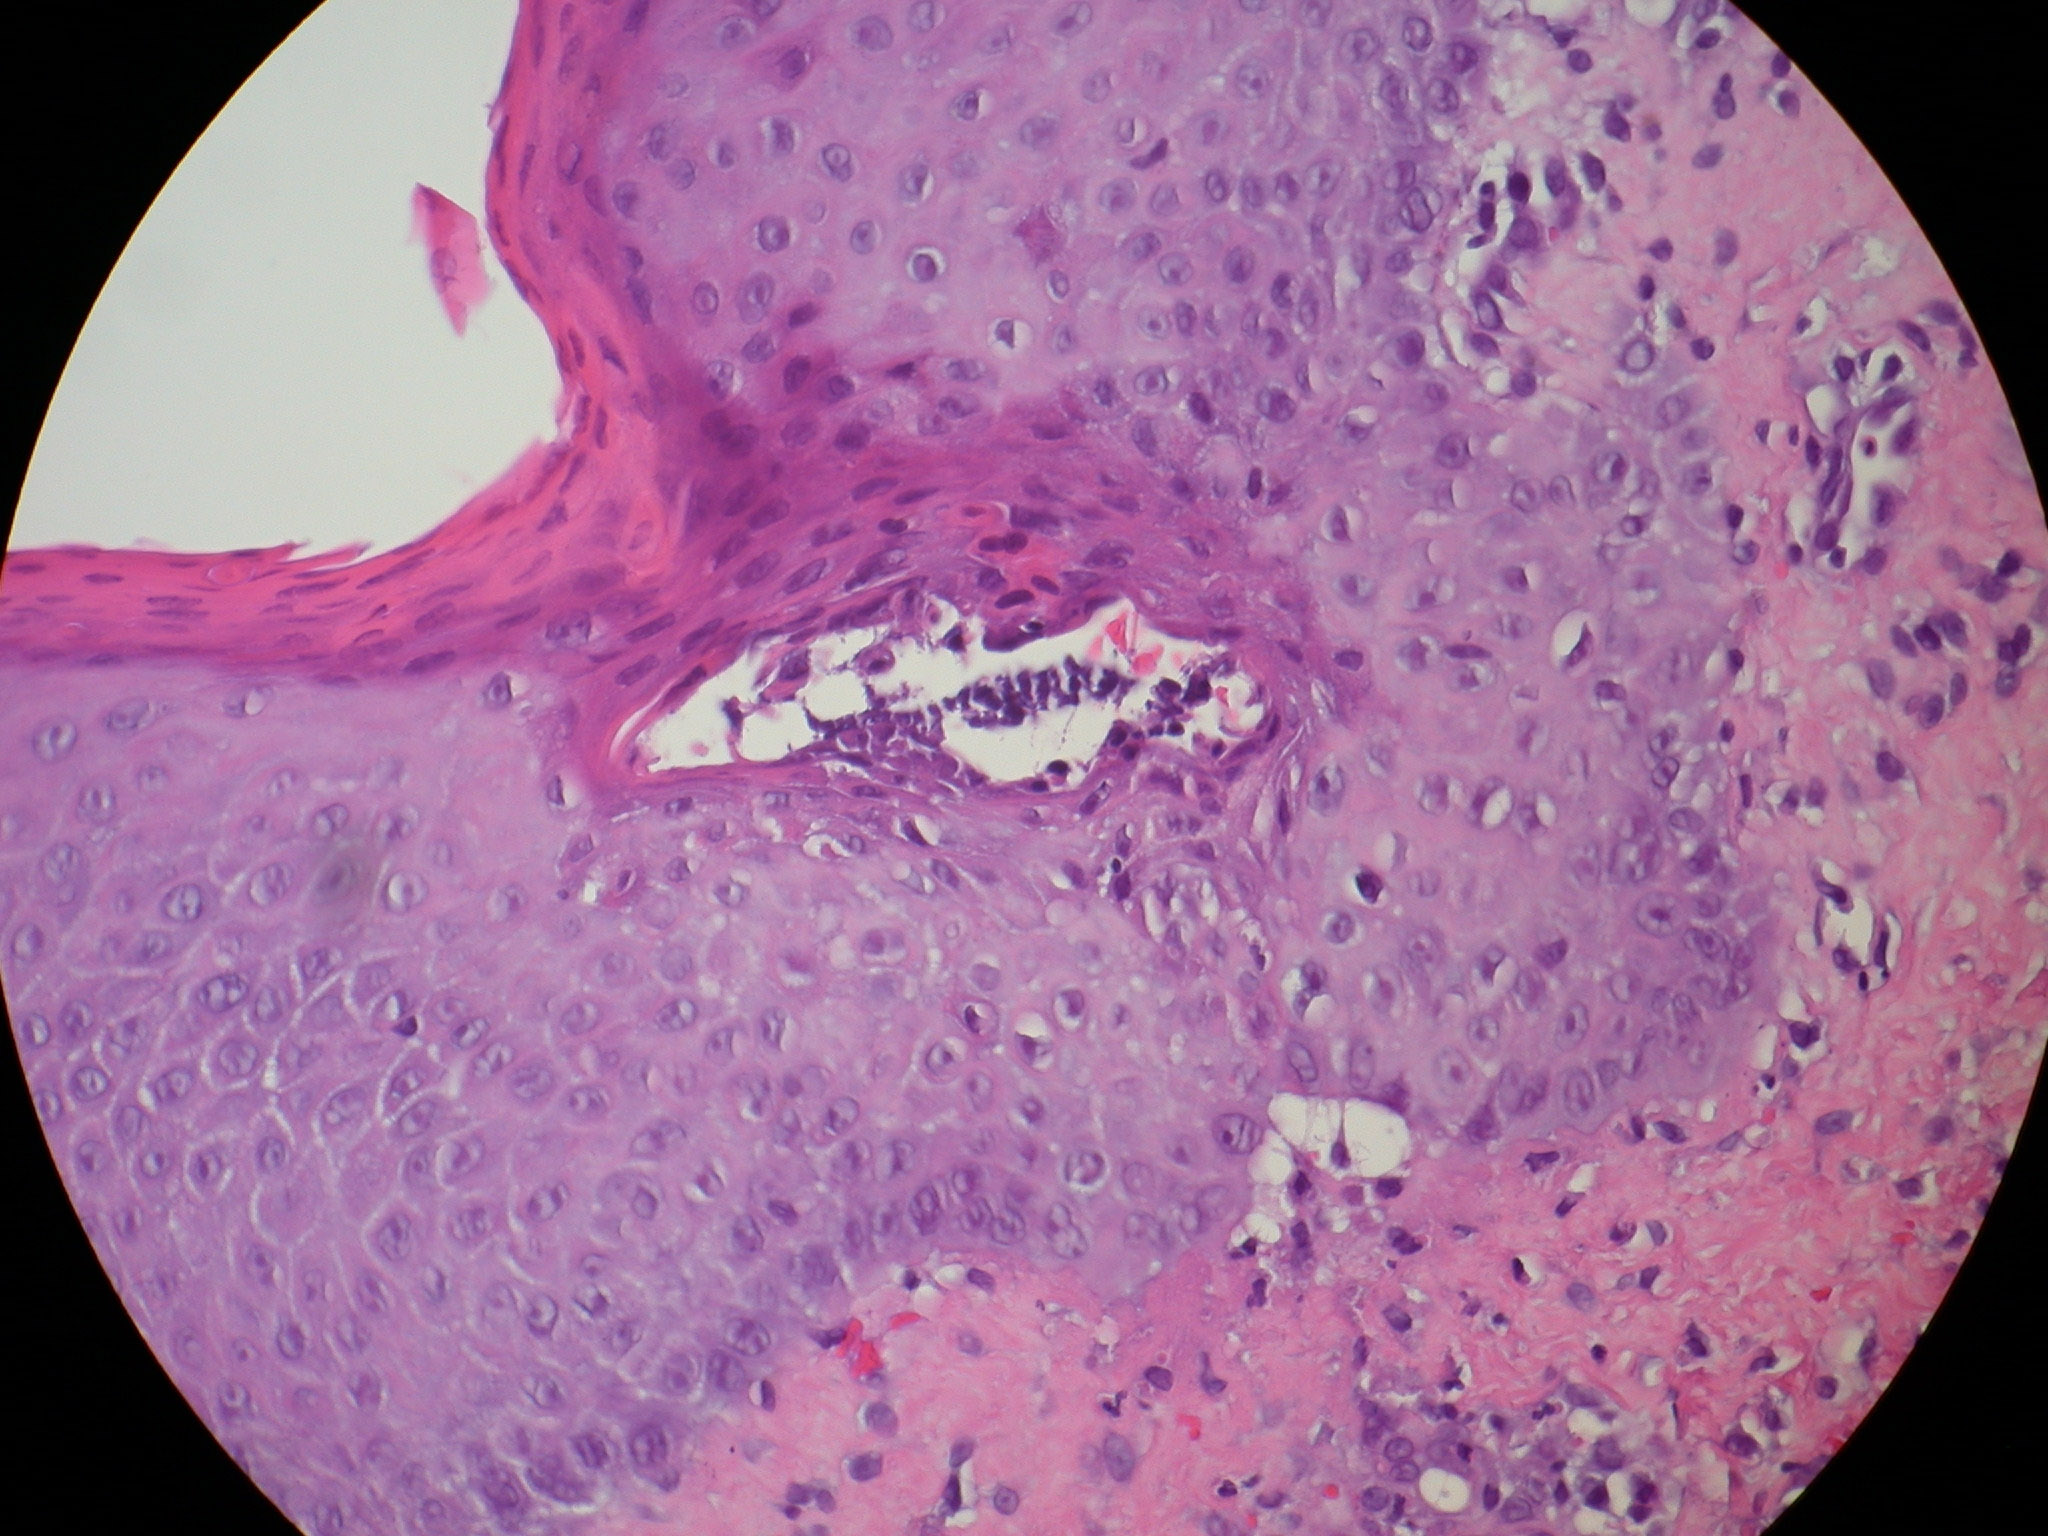

SPD may be associated with a monoclonal gammopathy, which most commonly is an IgA paraproteinemia. Some of these cases eventuate in an IgA myeloma and may have IgA squamous intercellular substance deposits. Histopathology. The pustules are subcorneal and contain neutrophils, with only an occasional eosinophil . |

The underlying slightly edematous stratum malpighii contains a small number of neutrophils. Only a few spongiform pustules are formed. In some instances, a few acantholytic cells are found in the base of the pustule, most likely because of proteolytic enzymes present in the pustular contents. They may be partially attached to the epidermis or may lie free in the pustule among the neutrophils. The dermal papillae contain dilated capillaries and a perivascular infiltrate composed of neutrophils and a few eosinophils and mononuclear cells. |

Ultrastructural Study. The edge of the pustules shows cytolytic changes in the upper epidermis, especially in the granular layer. Dissolution of the plasma membrane and of the cytoplasm of granular cells causes the formation of a subcorneal split. The transepidermal migration of neutrophils and their subcorneal accumulation are regarded as events secondary to the cellular destruction in the stratum granulosum seen in one study. |